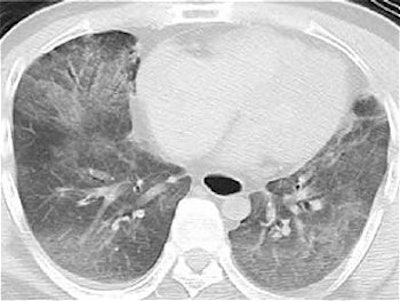

Twelve hours after confirmation of death, the postmortem MRI was performed for a closer examination of the myocardium. T2-weighted MR imaging of the heart showed high signal intensity in the anteroseptal and apical areas relative to the remainder of the myocardium, the authors explained.

![]() |

| T2-weighted image of postmortem MRI of the heart shows high signal intensity (arrows) in the anteroseptal and apical areas relative to the remaining myocardium. Inhomogeneous high signal intensity in both lungs is also shown. Shiotani S, Yamazaki K, Kikuchi K, Nagata C, Morimoto T, Noguchi Y, Suzuki M, Atake S, Kohno M, Ohashi N, "Postmortem Magnetic Resonance Imaging (PMMRI) Demonstration of Reversible Injury Phase Myocardium in a Case of Sudden Death from Acute Coronary Plaque Change" (Radiation Medicine, Vol. 23, No. 8, pp. 563-565, 2005, Figure1AB). |